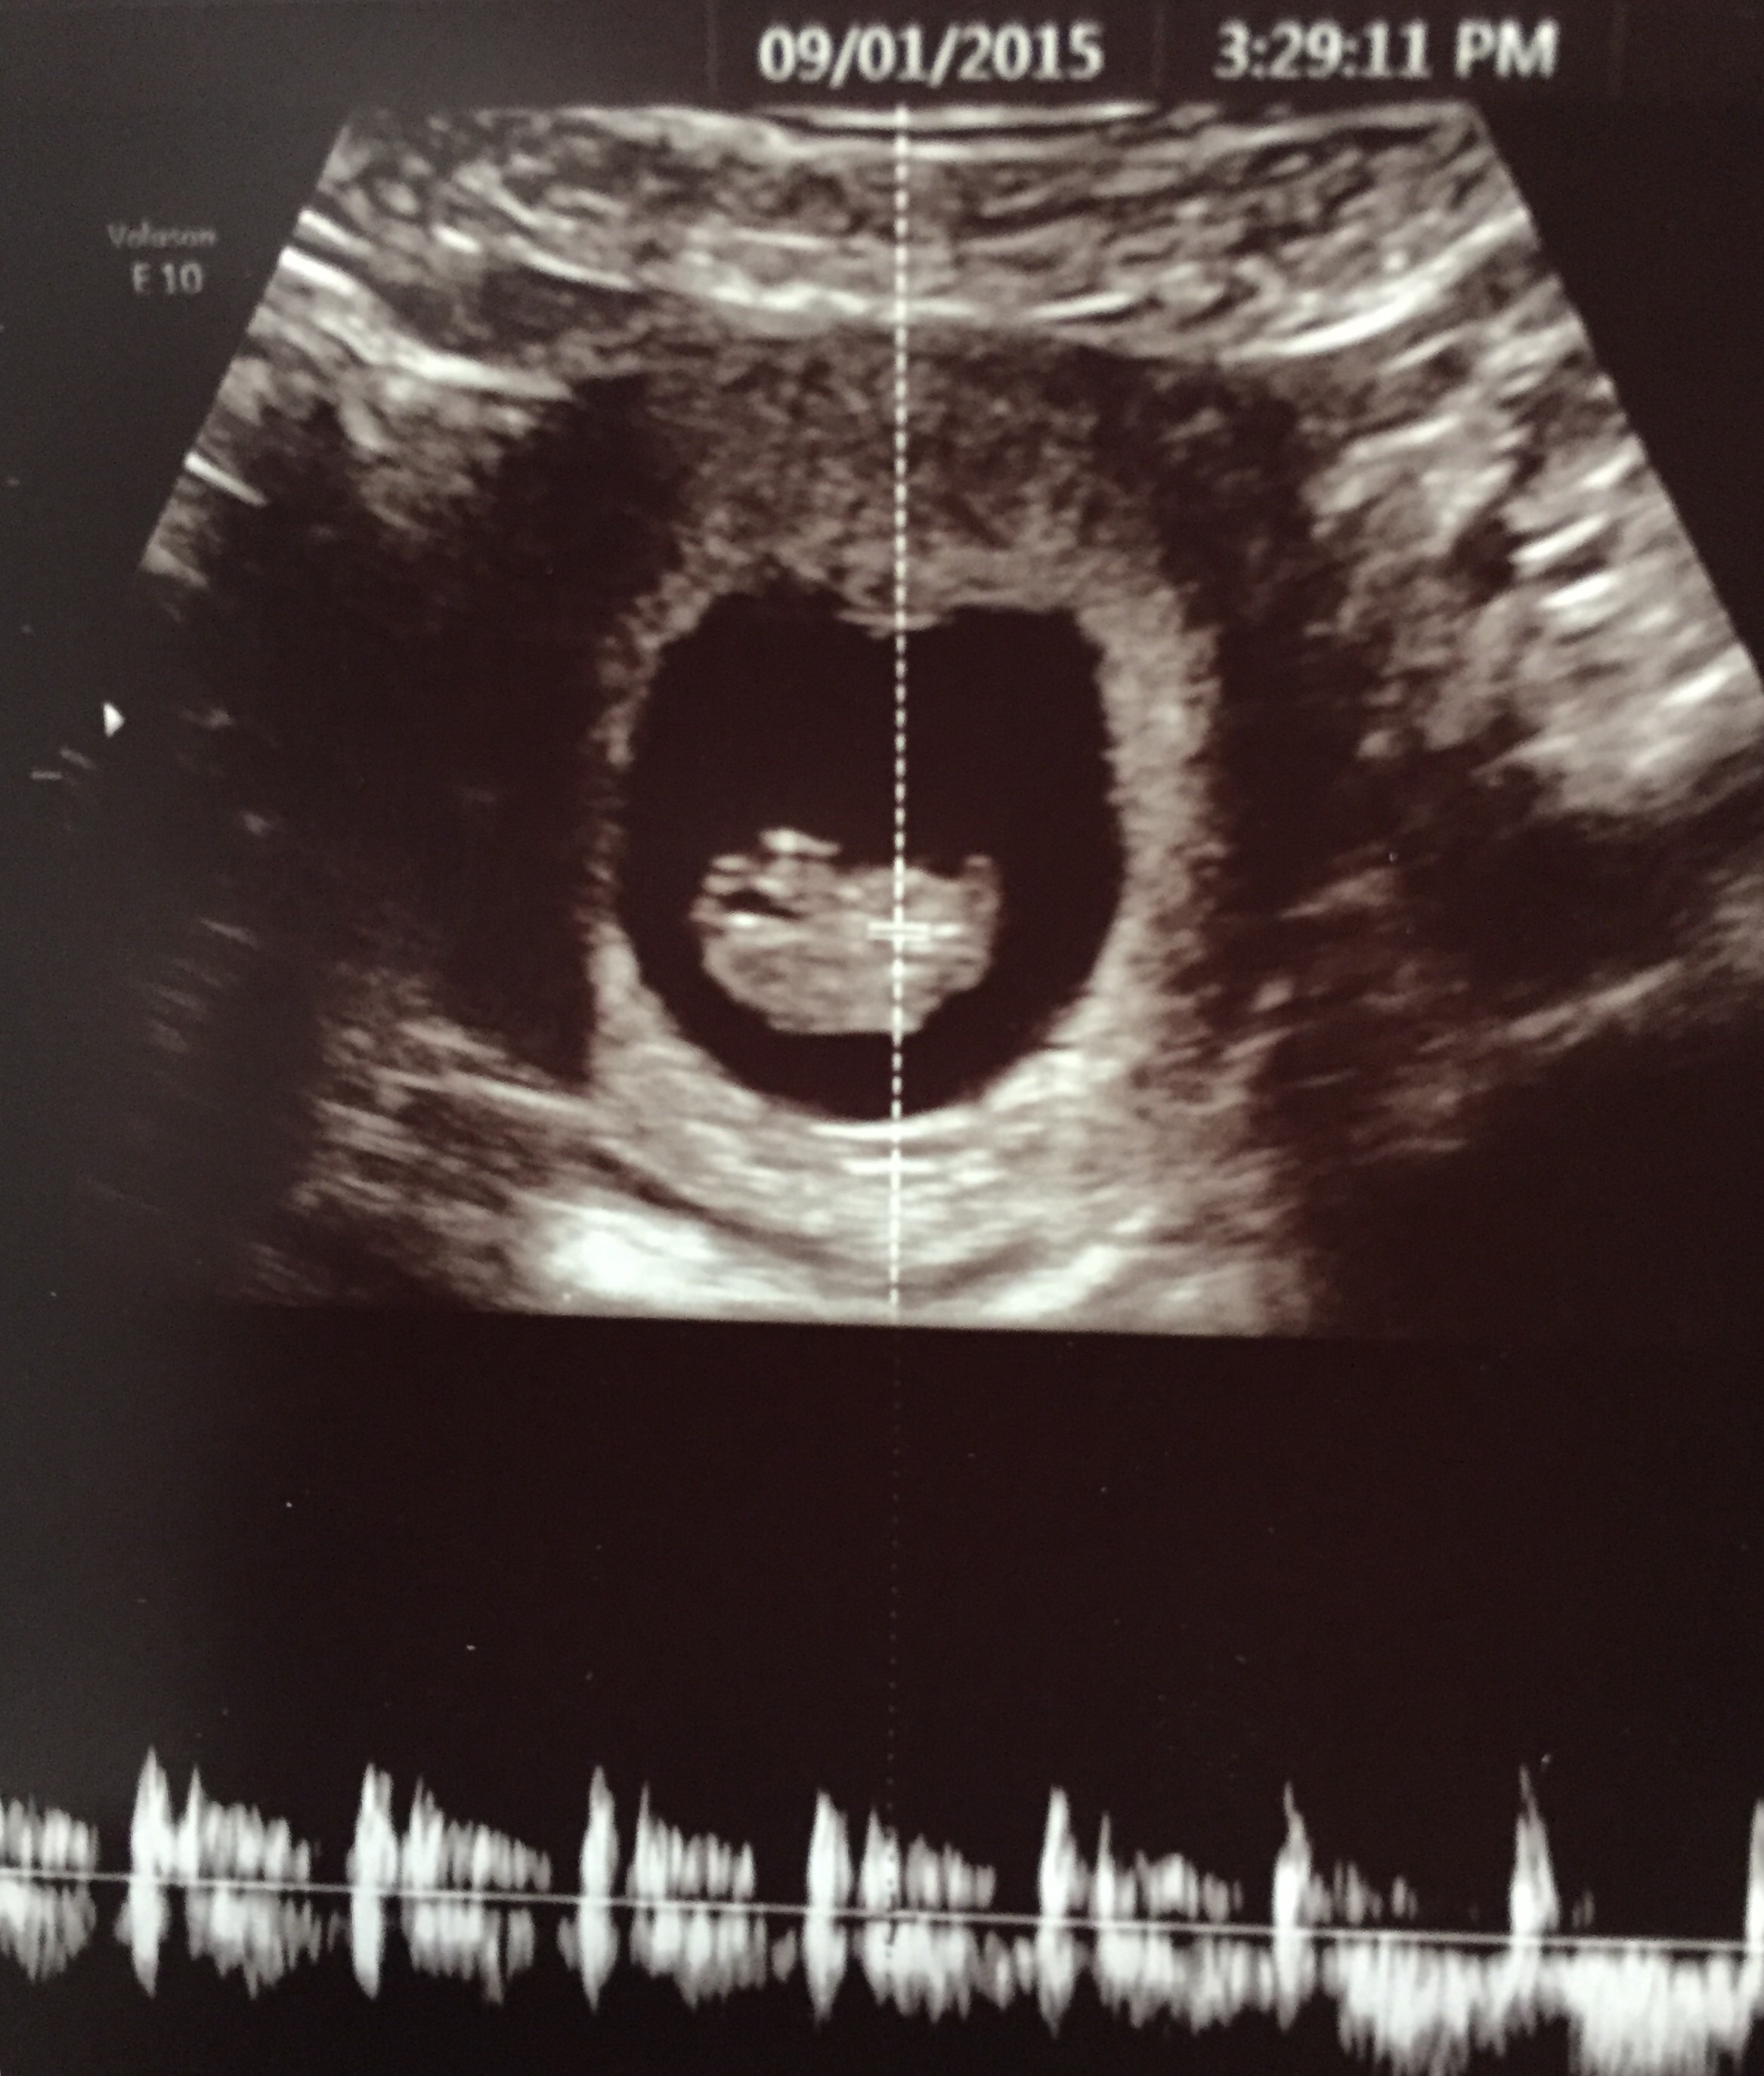

• My 9 week u/s on sept 1st! Posting a little late, but better late than never.